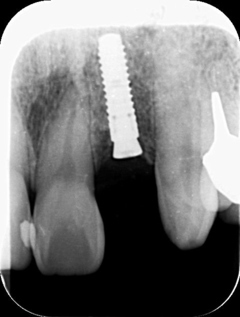

一時治ったと思っても、長い目でみると歯そのものの寿命を短くしてしまいます。

●大きく削ってインレーを詰めても細菌の取り残しがある→数年後、虫歯の再発